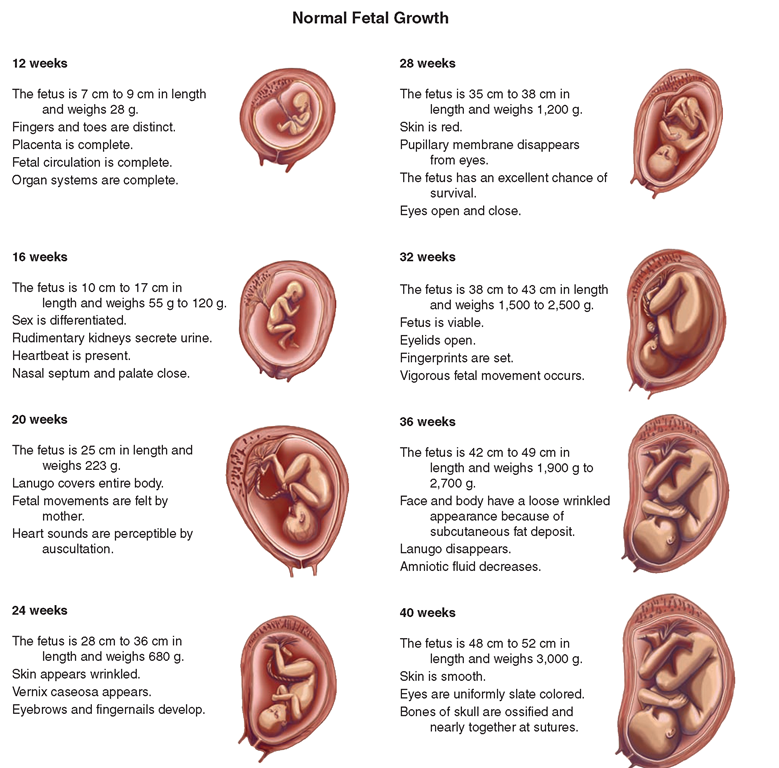

Looking for captivating what does a 2 month old fetus look like images? All, in collaboration with felix.edu.vn, presents a curated selection. Dive into the details for more.

what does a 2 month old fetus look like

We hope you enjoyed this article about what does a 2 month old fetus look like on felix.edu.vn. Let us know what you think in the comments, and discover more related content below.